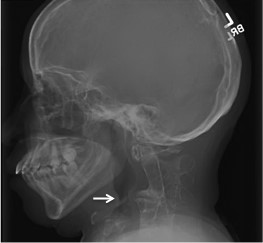

Given the severity of her sleep disordered breathing, a neck radiograph was ordered. On lateral view, fusion of cervical vertebrae C1-C3 was noted (Figure 1). A chest radiograph showed dextro-scoliosis without thoracic vertebral fusion (Figure 2A). Magnetic resonance imaging (MRI) of the cervical spine revealed fusion of the first three cervical vertebrae with degenerative changes throughout the cervical vertebrae, protrusion into the cervical canal, and reversal of normal cervical curvature (Figure 2B). Arnold-Chiari malformation was not seen. Spinal cord signal intensity was normal. MRI of the brain, and brainstem was normal.

A transnasal esophagoscopy was performed to further evaluate her airway. The standard endoscope was passed with ease through the mouth under direct visualization to the hypopharynx. Pulse oximetry revealed abrupt oxyhemoglobin desaturation when the scope was advanced into the cryopharyngeaus to the level of the white arrow in Figure 1. A pediatric endoscope was then used and passed without difficulty. No further abnormalities were encountered.

Figure 1: Lateral radiograph of this patient’s head and neck showing a cervical spinal deformity (white arrow) attributable to Klippel-Feil Syndrome.

Our patient did not have hindbrain anomalies. Figure 1 shows cervical vertebral fusion with vertebral body impingement on the posterior airway (which explains the need to use a pediatric endoscope during transnasal esophagoscopy). This airway narrowing, in combination with short neck, decreased neck extension and scoliosis are the syndrome specific factors contributing to this patient’s sleep disordered breathing. In our patient mild retrognathia and overweight are the non-syndrome related factors contributing to her severe disordered breathing.

In addition to her short neck and scoliosis, other contributions to her severe sleep disordered breathing associated with Klippel-Feil Syndrome probably included impingement of a vertebral body bony abnormality on the posterior airway (white arrow, Figure 1).